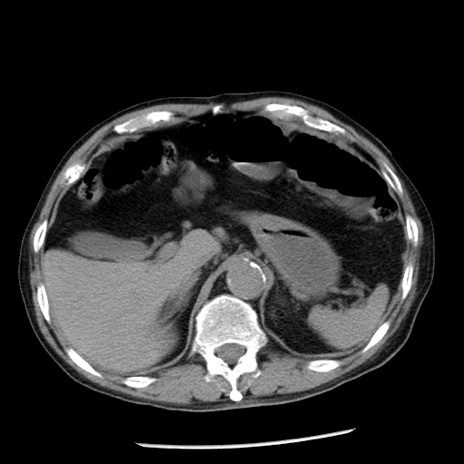

症例26(横断像)

【症例】80歳代男性

【主訴】嘔吐

【現病歴】昨晩2回嘔吐あり、今朝になっても嘔吐あり。来院。

【既往歴】胃潰瘍

【身体所見】意識清明、BT 37.6℃、BP 166/95mmHg、HR 100bpm、SpO2 97%、腹部:平坦・軟、腸蠕動音聴取良好、圧痛なし。

【データ】WBC 21900、CRP 1.46